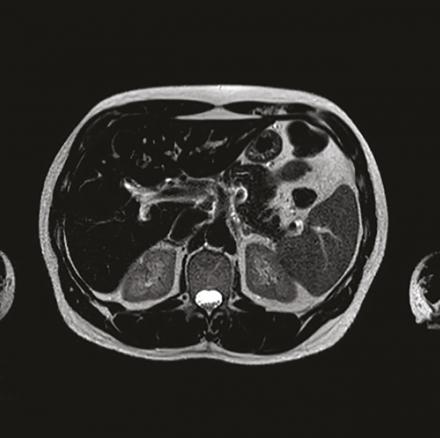

Cet homme de 53 ans suivi pour un syndrome anxiodépressif et un alcoolisme sevré, consultait pour une asthénie et un « burn-out ». L’interrogatoire notait que la fatigue s’estompait les week-ends et durant les vacances, et ne rapportait pas d’autre plainte fonctionnelle. Une biologie antérieure montrait une cytolyse hépatique prédominant sur les alanine aminotransférases (1,5 fois la valeur normale). Dans ce contexte, un bilan systématique était prescrit avec un contrôle thyroïdien et ferrique, montrant une hyperferritinémie à 3 756 µg/L. Le bilan complémentaire notait un coefficient de saturation de la transferrine (CST) à 90 %, une surcharge ferrique hépatique en imagerie par résonance magnétique (IRM, fig. 1 et 2 ) à 392 µmol/g, et une mutation postive C282Y homozygote. Le diagnostic d’hémochromatose héréditaire a été annoncé au patient au cours d’une consultation dédiée, en lui expliquant la nécessité d’une saignée hebdomadaire avec comme objectif une ferritinémie inférieure à 50 µg/L et l’intérêt d’un dépistage familial. L’évolution est marquée par une stabilisation de l’asthénie permettant à ce patient sportif une reprise partielle de ses activités physiques.

L’asthénie est un motif fréquent de consultation en médecine générale.1 Il n’existe pas de recommandations pour un bilan type. Un examen clinique précis vise à ne proposer un bilan qu’aux patients suspects d’une maladie sous-jacente, tels que notre patient ayant une anomalie du bilan hépatique. L’hémochromatose liée au gène HFE (type 1)2 est une maladie génétique de surcharge en fer (mutation C282Y). Le retard diagnostique est fréquent, devant des symptômes peu spécifiques, mais un diagnostic précoce permet de mieux prévenir les complications. Le CST et l’IRM sont les examens de référence. Les facteurs de risque de survenue d’une complication sont la consommation d’alcool et les viroses hépatotropes. Le traitement repose sur des saignées.